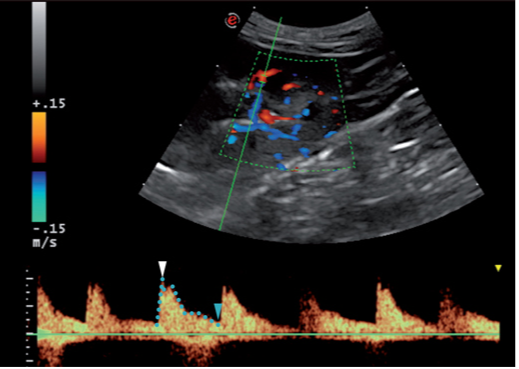

一项脉冲多普勒关于肾脏血管形成的研究显示,弓状动脉或小叶间动脉具有代表性,其足以显示肾脏的大致情况。同样地,可以使用彩色多普勒在皮质延髓交界处定位弓状动脉。在启动测量卡尺后,通过一个1-2mm大小的抽样窗口,集中在动脉上记录几个流动波形(至少3个)并取得平均值。

总体来说,超声波设备已经包含自动计算这些指数的程序,包括最大收缩压,最小舒张压和平均速度(图1)。另外,早期收缩加速度(ESA)这一指数被定义为评估多普勒波形的变化。

血管指数可间接测量肾脏高血压以及对血管阻力进行预估。阻力指数(RI) 和搏动指数(PI)计算公式是: RI=(收缩期峰值流速-舒张末期血流速度)/收缩期峰值流速; PI=(收缩期峰值流速-舒张末期血流速度)/时间平均流速。